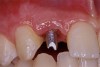

Periapical radiographs were taken to help determine the mesial-distal inclinations of the adjacent tooth roots (Figure 1). The radiographs revealed a serious issue, convergent roots for the right canine and right central, which eliminated that area as a potential implant-receptor site. The space between the left central and canine teeth was minimal, although the roots were relatively parallel. Clinical examination (manual palpation of the root eminences superiorly to the vestibule on the right side) confirmed the root convergence (Figure 2A). The flat, wide zone of the keratinized tissue and lack of interdental papilla was evident for the missing right lateral incisor. There was a marked difference in clinical appearance for the left lateral, which could impact the eventual plan of treatment (Figure 2B). Other significant clinical findings included bilateral facial bone concavities, which existed as a result of the congenitally missing tooth roots. As a diagnostic cue to the underlying bone topography, it is important to follow the demarcation between attached and unattached gingival tissue, and note the crestal width of the available keratinized tissue (Figure 2C).

Figure 1  Pretreatment radiographs revealed convergent roots for the right canine and right central.

Figure 1